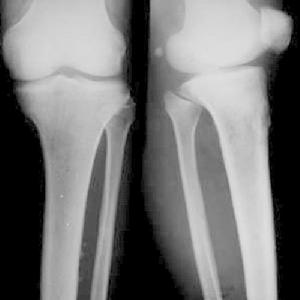

發病部位以下肢長骨最多見,主要位於膝關節周圍。股骨遠端乾骺端最常見,其次為脛骨近端及遠端乾骺端腓骨近端乾骺端也常見比較少見的部位還有股骨近端乾骺端及上肢骨。單發組織細胞纖維瘤在短骨及扁骨非常罕見。

病變多在乾骺端,可隨病情發展,病變可以逐漸向骨幹移行,多位於一側皮質內或骨膜下,病變進一步發展可侵入髓腔使整個乾骺端或骨幹均有病變。

組織細胞纖維瘤有典型的X線特徵有些學者認為不需經組織學檢查,就能對大多數病例作出正確診斷。病變始於長骨的乾骺端,靠近骺板,且總在一側皮質上膨脹、偏心性隨骨的生長發育病變可以逐漸向骨幹移行,病灶內為界限清楚透亮陰影,呈分葉狀卵圓形,周邊有一硬化緣。病變縱軸與長骨一致,病變小自1cm,最大可達15cm。病變發展有侵入髓腔、破壞整個乾骺端導致整個皮質變薄,造成病理性骨折。病變可隨骺板生長而擴大骺閉合後病變有可能停止生長